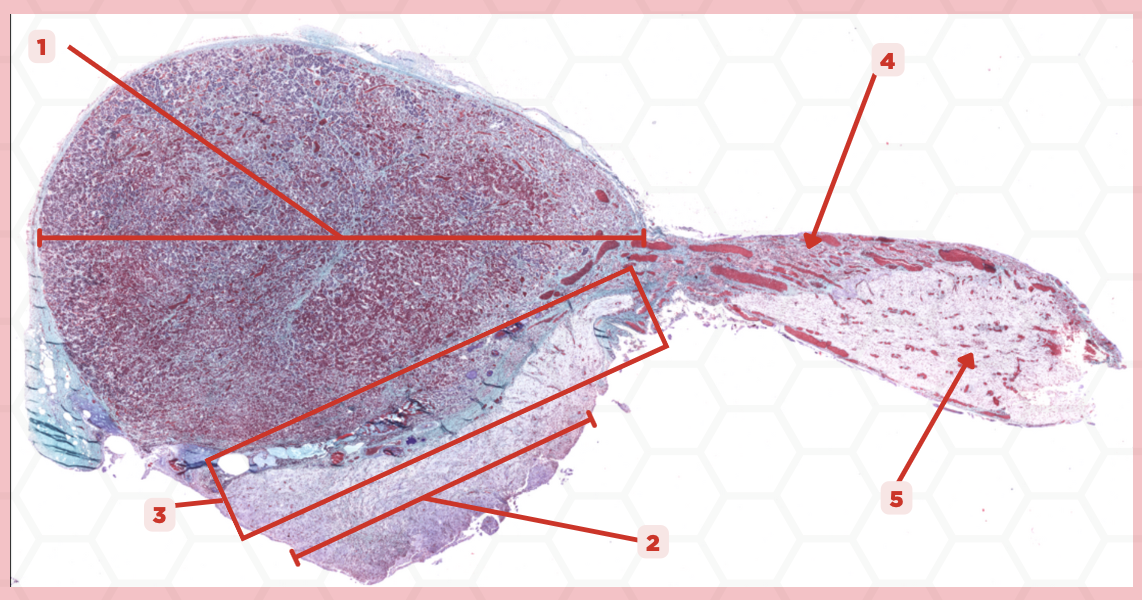

Adenohypophysis

What does #1, #4, and #5 form?

Pituitary

Identify the specimen.

Intermediate Lobe

Identify the structure labeled as 1.

Posterior Lobe

Identify the structure labeled as 2.

Pituitary Stalk

Identify the structure labeled as 3.

Pars Tuberalis

Identify the structure labeled as 4.

Anterior Lobe

Identify the structure labeled as 5.

Neural Ectoderm

What ectoderm is #2  derived from?

Oral Ectoderm

What ectoderm #1, #3, & #4 derived from?